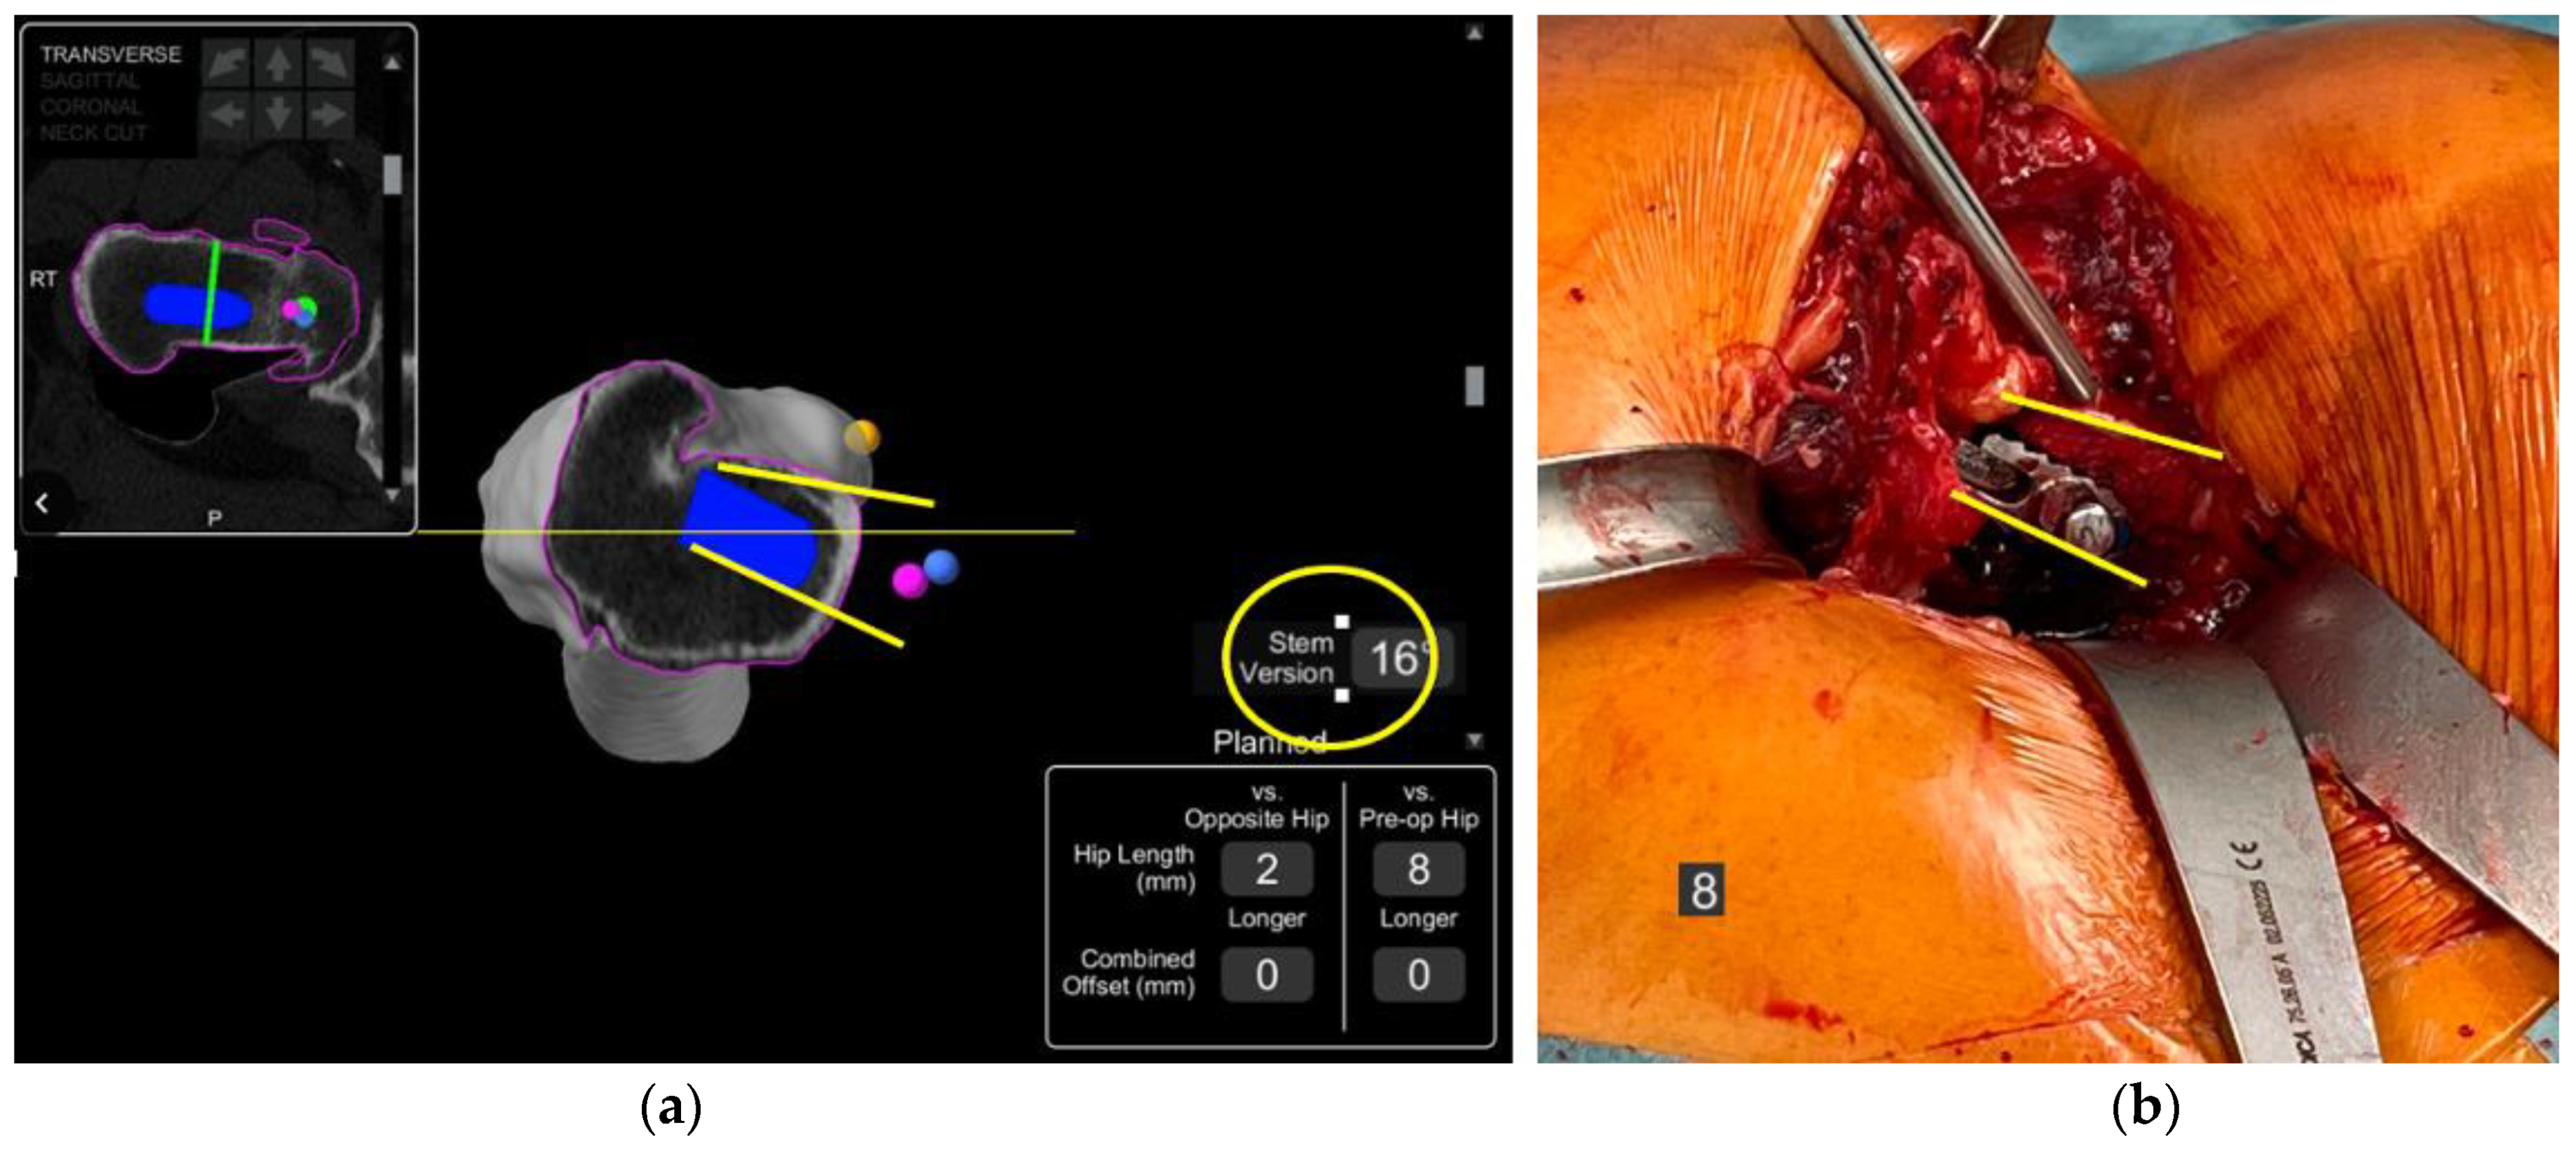

- In this case, the native femoral retroversion (−6 degrees) posed a challenge in avoiding impingement (Figure 7). Upon assessing VROM, bone-on-bone and implant-on-implant impingement in deep flexion were noted (Figure 8). Using the robotic software, the planned femoral version was corrected to +16 in the femoral broach (Figure 9a,b).